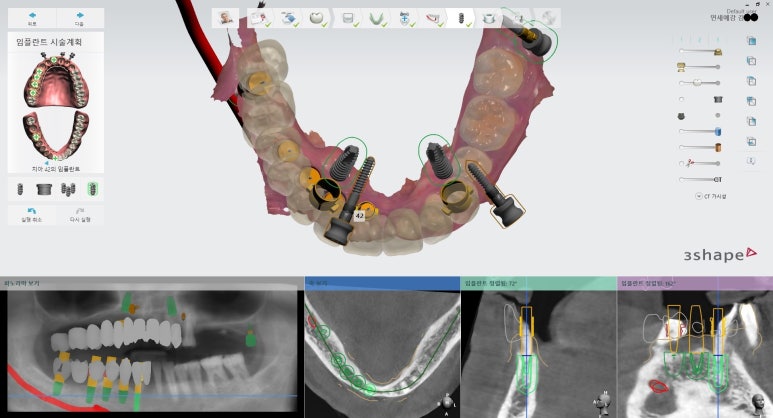

아래는 실제 저희 연세예감치과에서 내비게이션 인플란트를 시술한 환자분들의 모의시술 사진입니다.

빨간 색은 하악에 있는 큰 신경관으로 이 신경관을 건드릴 경우 감각 이상 등이 올 수 있어 이 신경관을 건드리지 않고 수술하도록 디자인되었습니다.